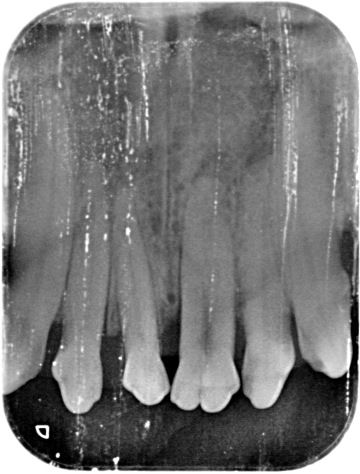

Diagnostics - intraoral X-ray

The x-ray of your pet's teeth is similar to that of humans. An x-ray machine using a small amount of radiation is used to view the inside of your dog's teeth and those areas below the gum line that are hidden. Unlike humans, animals must be under general anesthesia for a dental X-ray, as it is practically impossible to get them to hold the plate in their mouth and not bite into it. You can read more about the anesthesia itself and what it all entails here.

Animals just can't tell us when their teeth are sick and some never show that they are in pain. In many cases, an intraoral x-ray is the only way we can tell that your pet has a serious dental problem that can be treated and the discomfort alleviated.

It should be noted that quality dental treatment requires x-rays of the teeth. Without an x-ray of the teeth, it is practically impossible to assess the condition of the periodontium, and diseases that occur below the level of the gums are invisible to the human eye.